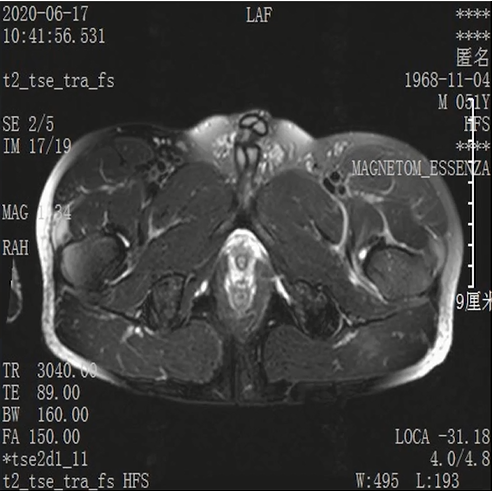

Lisfranc损伤在多发伤病人中常常容易漏诊,大约为 20-30%的漏诊率!